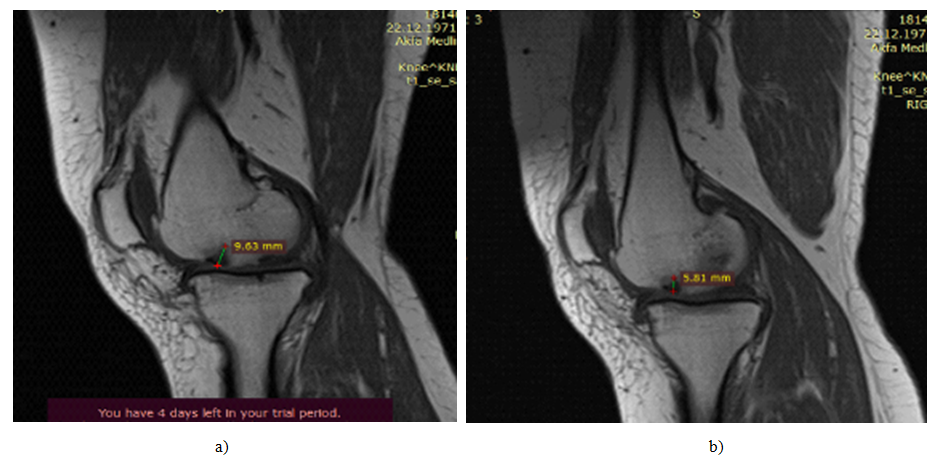

All patients included in the study were examined 1, 3 and 6 months after the introduction of SVF. A single intraarticular injection of SVF cells from platelet-rich plasma was accompanied by a gradual decrease in pain syndrome, assessed on the VAS and KOOS scales (subscale "Pain") (Fig. 1). At the same time, all patients noted a decrease in pain after 1 month after the introduction of cells, which persisted up to 6 months of observation. According to VAS, the severity of the pain syndrome gradually decreased during the entire follow-up period, reaching a twofold decrease by 6 months. The survey of patients on the KOOS scale also demonstrated a decrease in the severity of the main symptoms of the disease, a decrease in difficulties in performing daily activities, an increase in the possibility of sports and an improvement in the quality of life associated with the affected joint. At the same time, the clinical improvement was accompanied by positive dynamics according to ultrasound and MRI of the joints. Indeed, after 3 months. after the introduction of SVF cells, an increase in the thickness of hyaline cartilage in the affected joints was recorded in all patients (M±m 1.42±0.04, p<0,01).

Figure 2. MRI picture of synovial fluid volume. a)-before surgical intervention. b)-after 6 months of surgical intervention.

Figure 3. MRI picture of cartilage defect, osteophyte volume. a)-before surgical intervention. b)-after 6 months of surgical intervention